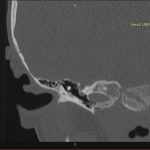

- Diagnosticul traumatismelor de bază de craniu

- Diagnosticul fracturilor:

-

- Unice

- Multiple

- Cu înfundare

- Complexe cranio-sinusale

- Complexe cranio-etmoidale

- Complexe cranio-orbitare

- Complexe cranio-faciale